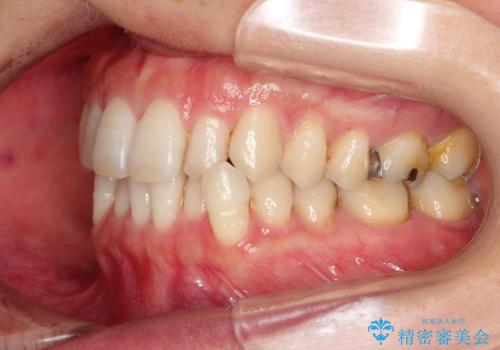

八重歯のインビザライン矯正治療

- 下顎の八重歯と、上下のクロスバイトを気にして来院された患者様です。

インビザラインを用い、下顎全体の後方移動、IPR(歯と歯の間を削る)と歯列全体を拡大させることで、歯並びを整えていくこととしました。